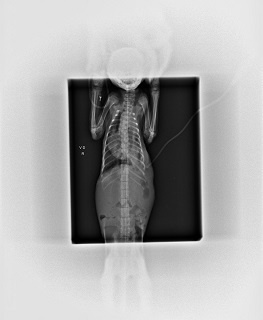

照X光發現小貓脊椎有超過三處的斷裂,

比照外部傷口後研判是被野狗給咬傷造成的,

而這個咬傷造成小貓的橫隔膜破裂,

也就是說腹部的臟器全都往上移位到胸腔,

心臟和肺部嚴重被擠壓,

造成小貓呼吸上開始有些許困難,

觀察小貓的病情後因怕小貓胸腔感染多時先留了小貓下來做血液檢驗.X光等檢查,

做橫膈荷尼亞疝氣手術治療,

解釋開刀時發現胸腔已有化膿跡象,

在嬌小七百克的小貓身上就抽出了70ml的膿液,

也在胸腔引了一個導流管,

讓小貓胸腔剩餘的膿液可以排除動物近況說明: 目前小貓手術後已甦醒,